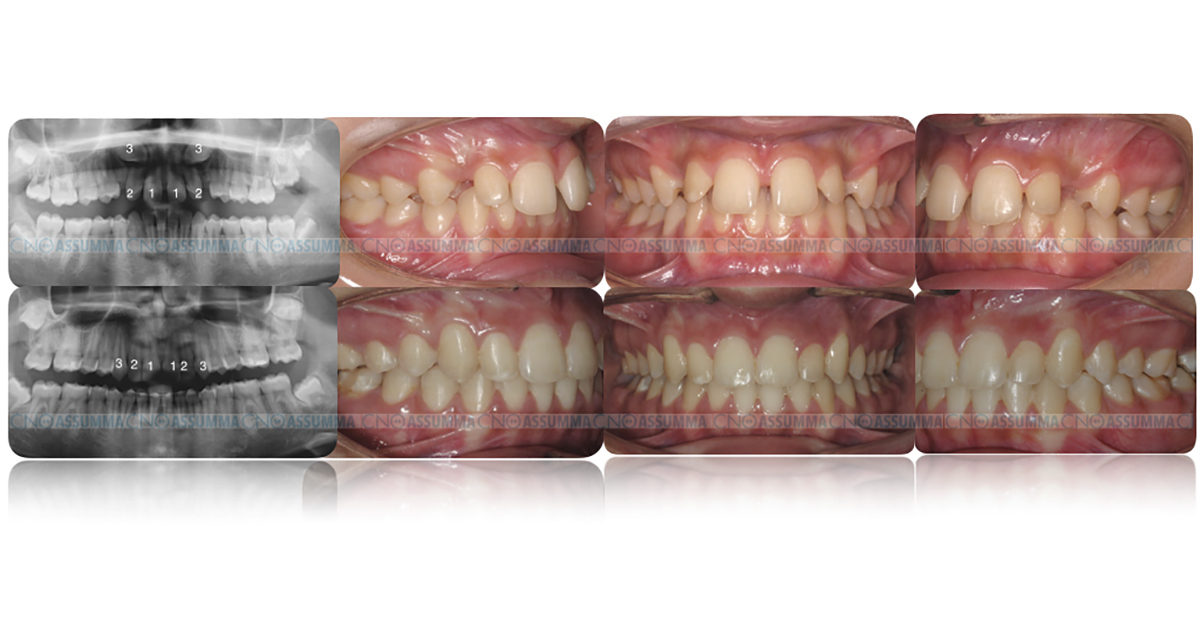

La diagnosi è sia clinica (palpazione della bozza canina, assenza in arcata del canino, persistenza del canino deciduo) che radiologica (OPT, Teleradiografia latero-laterale, CBCT).

- esposizione chirurgica e disinclusione attraverso un trattamento ortodontico dell’elemento dentario fino ad ottenere il suo corretto posizionamento in arcata.

L’esito della terapia ortodontico-chirurgica dell’inclusione del canino è spesso buona. Tuttavia, possono esserci complicanze come il riassorbimento delle radici dei denti adiacenti, problemi gengivali come le recessioni, e nei casi più gravi l’anchilosi del dente che comporta l’estrazione e sostituzione protesica dell’elemento incluso.